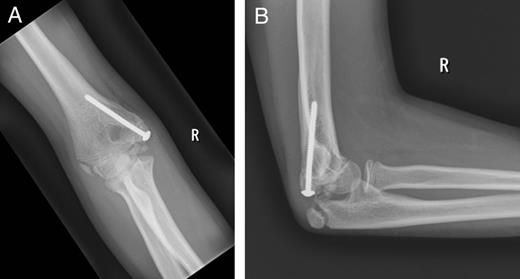

At 5 months follow-up, the patient had full range of movement of the stable elbow with completely recovered ulna nerve function. The plain radiographs confirmed that the fracture healed (Fig. 3A and B).

Plain radiographs showing the healed fracture of the right elbow at 5 months: (A) anteroposterior view and (B) lateral view.